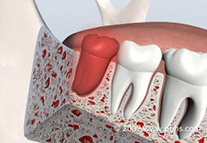

• Bone Grafting

• Overview

Bone Grafting